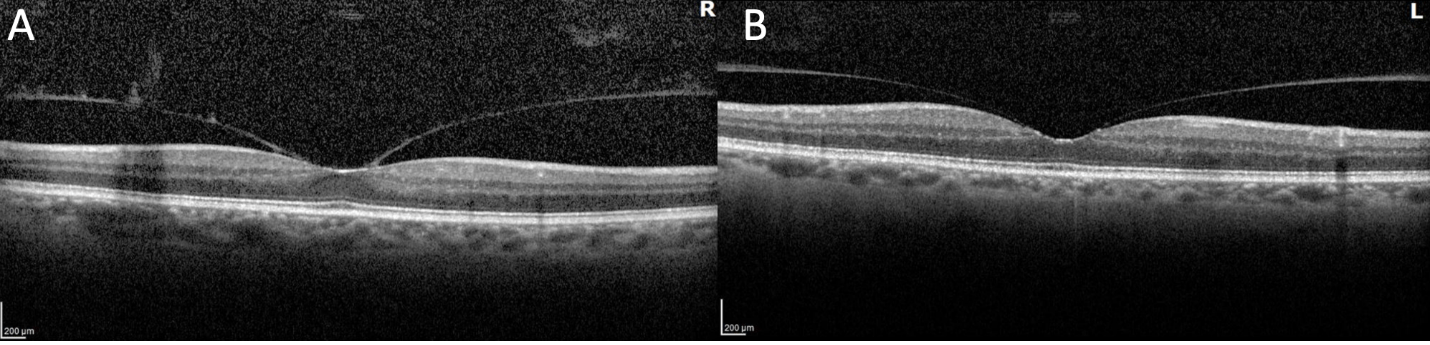

The patient subsequently underwent genetic testing, which showed a missense mutation in the transthyretin gene consistent with familial systemic amyloidosis. Late-phase ICG showed characteristic hyperfluorescent spots along the choroidal vessels, and OCT showed needle-shaped deposits on the retina (Figure 3).

<p>Figure 3. OCT of the right eye (A) shows the characteristic needle-shaped deposits on the retina compared with the normal left eye (B).</p>

Figure 3. OCT of the right eye (A) shows the characteristic needle-shaped deposits on the retina compared with the normal left eye (B).

Diagnosing ocular amyloidosis requires a high degree of suspicion. Although PPV remains the standard to confirm vitreous involvement, several imaging features have been described that can aid clinicians in these cases. Choroidal amyloid angiopathy, which appears as hyperfluorescent streaks on late-phase ICG, has been described in several studies.6,7 At least 10 minutes of staining are required to demonstrate these findings, with maximal staining seen around 12.5 minutes.6 On OCT, needle-shaped deposits, presumably depicting amyloid deposition on the retina, have been described, which can persist even after PPV.8